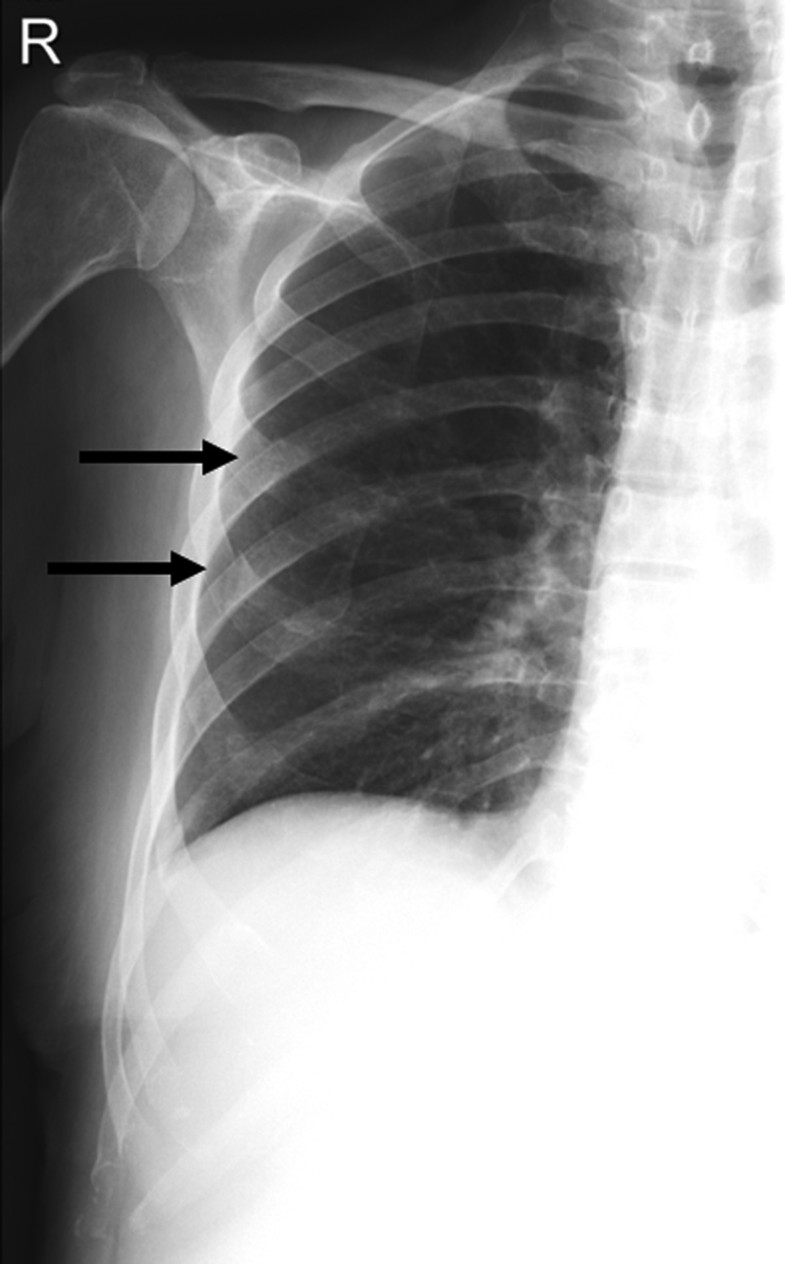

CXR (Chest X r ay) showing fractures of left 6 th , 7 th and 8 th ribs

CXR (Chest X r ay) showing fractures of left 6 th , 7 th and 8 th ribs Ribs Xray Sid Web there are 12 pairs of ribs. * may need to do lower obliques for better visualization of ribs, especially if this is the affected. (bilateral see next page) • pa erect chest •. Web if doing a bilateral rib examination, place ir crosswise for large patients for both above and below diapragm ribs to ensure that. Web the ribs. Ribs Xray Sid.